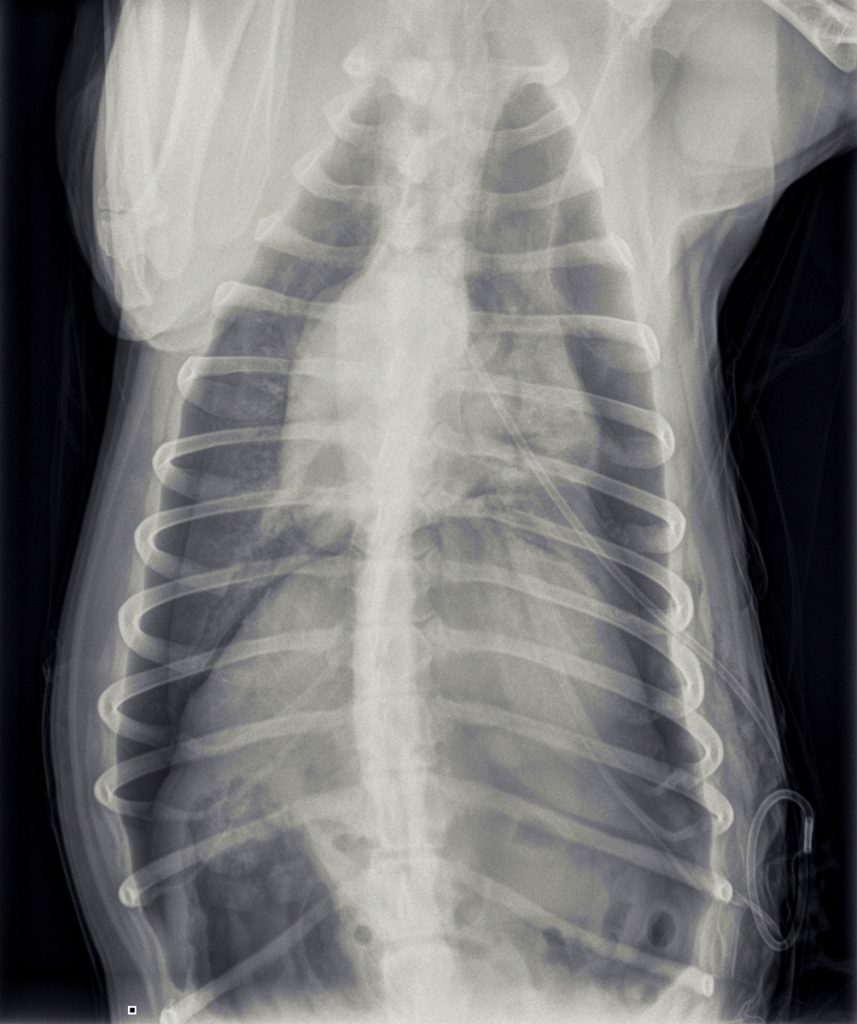

In overleg met de eigenaar van Jessie is besloten om röntgenfoto’s te maken.

Hierop was te zien dat er sprake was van een beiderzijdse klaplong. Dit betekent dat Jessie’s longen vrijwel geen lucht meer bevatten en ingeklapt in de borstholte lagen met lucht eromheen. Normaal hoort er geen lucht tussen de longen en de borstwand aanwezig te zijn.

In de loop van de volgende dag werd de hoeveelheid lucht, die we konden afzuigen, steeds minder en ging het steeds beter met Jessie. Omdat het voor Jessie prettiger was, ging Jessie het einde van de dag naar huis. Jessie was enorm blij om haar baasje te zien en was eigenlijk wat te wild in de begroeting. Na 1,5 uur belde de eigenaar ons op, dat het niet goed ging, dus Jessie moest gelijk terugkomen. Jessie was weer erg kortademig. Dit was verbazend, gezien hoe goed het eigenlijk ging. We hebben nieuwe röntgenfoto’s gemaakt en zagen weer veel lucht. Mogelijk was er toch weer iets gaan lekken door de eerdere activiteit.

De drain lag vrij ver naar voren, tot nu toe was dat geen probleem geweest. Maar voor de zekerheid hebben we de drain wat verplaatst. Dit was even erg spannend, omdat er daarbij wat lucht langs de drain naar binnen ging. Jessie kon niet meer ademen en raakte in paniek. Gelukkig konden we haar lang genoeg in de houdgreep houden om de lucht weer uit de thorax te zuigen. Opvallend was dat we veel lucht eruit konden zuigen en dit bleek elke keer het geval wanneer we haar borstholte leegzogen.